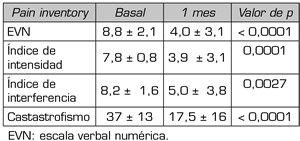

En la Tabla II se muestran los resultados encontrados en los pacientes controlados al mes (n = 39). Se pueden observar los valores de la EVN, de los índices de intensidad e interferencia del dolor, y los valores del catastrofismo total, en la situación basal y en el control al mes.

Tabla II. Escalas de valoración numérica, índices de intensidad, interferencia basales, catastrofismo total basales y al mes del tratamiento en el total de los pacientes controlados (n = 39). Se expresa como la media y desvío estándar

Se observó que todos estos aspectos disminuyeron de manera estadísticamente significativa, aunque clínicamente poco relevante, después de un mes de la inyección epidural de esteroides. El EVN pasó de 8,0 ± 2,0 a 6 6 ± 3,2 con un porcentaje de cambio de 17 % (p = 0,01), el índice de intensidad de 7,6 ± 0,8 a 5,9 ± 3,6 (22 % de porcentaje de cambio, p = 0,002) el índice de interferencia, de 7,8 ± 1,1 a 6,7 ± 4,3 (14 % de cambio, p = 0,01) y el catastrofismo total de 38 ± 11 a 30 ± 17 (21 % de cambio, p = 0,003).

En la Tabla III se detallan los valores de la EVN, de los índices de intensidad e interferencia del dolor, y del catastrofismo total, en la situación basal y en el control al mes, encontrados en esos 16 pacientes respondedores.

Tabla III. Escalas de valoración numérica, índices de intensidad, interferencia basales, catastrofismo total y al mes del tratamiento en los pacientes respondedores (n = 16). Se expresa como la media y desvío estándar

En esa población de pacientes respondedores, se observa que todos esos aspectos disminuyeron marcadamente. El EVN pasó de 8,8 ± 2,1 a 4,0 ± 3,1 con un porcentaje de cambio de 54 % (p < 0,0001), el índice de intensidad de 7,8 ± 0,8 a 3,9 ± 3,1 (50 % de porcentaje de cambio, p = 0,0001) el índice de interferencia, de 8,2 ± 1,6 a 5,0 ± 3,8 (40 % de cambio, p = 0,0027) y el catastrofismo total de 37 ± 13 a 17,5 ± 16 (57 % de cambio, p < 0,0001) (Figuras 5 y 6).